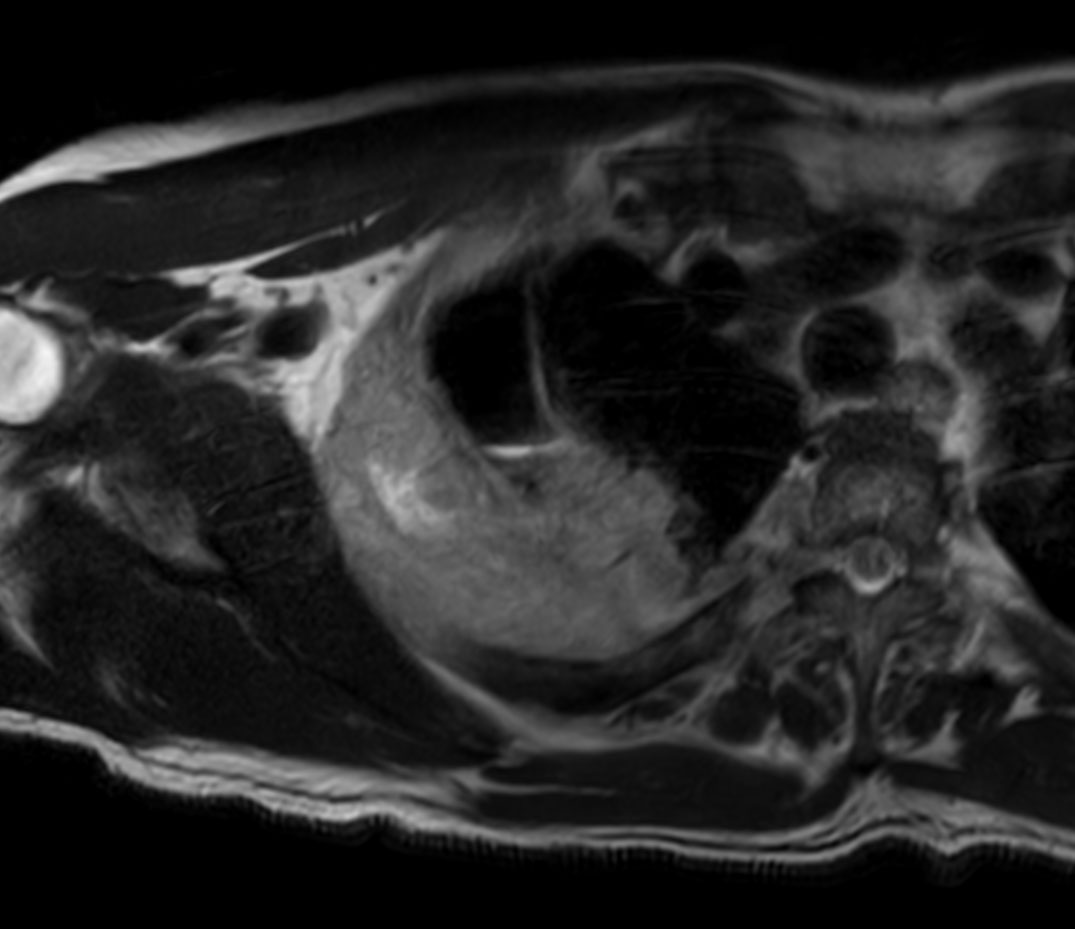

Coronal T1w TSE

Axial T1w TSE